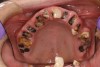

When smoked, methamphetamine produces highly toxic and corrosive fumes of lithium, muriatic, and sulfuric acids that can destroy enamel rapidly. With continued use, methamphetamine can produce severe, rampant caries, similar to early childhood caries. Patients have reported noticing changes in the appearance of tooth structure in as little as 3 months of use. The affected surfaces are the buccal and labial smooth surfaces, as well as the interproximal surfaces (Figure 1 through Figure 3). Because in the general population the vast majority of decay is found in the posterior molars, when someone presents with rampant anterior lesions it should be a red flag for methamphetamine use.5

Figure 1  DEVASTATING EFFECTS When smoked, methamphetamine produces highly toxic and corrosive fumes of lithium, muriatic, and sulfuric acids that can destroy enamel rapidly. With continued use, methamphetamine can produce severe, rampant caries. When someone presents with rampant anterior lesions it should be a red flag for methamphetamine use.

Figure 1

Figure 2  DEVASTATING EFFECTS When smoked, methamphetamine produces highly toxic and corrosive fumes of lithium, muriatic, and sulfuric acids that can destroy enamel rapidly. With continued use, methamphetamine can produce severe, rampant caries. When someone presents with rampant anterior lesions it should be a red flag for methamphetamine use.

Figure 2

Figure 3  DEVASTATING EFFECTS When smoked, methamphetamine produces highly toxic and corrosive fumes of lithium, muriatic, and sulfuric acids that can destroy enamel rapidly. With continued use, methamphetamine can produce severe, rampant caries. When someone presents with rampant anterior lesions it should be a red flag for methamphetamine use.

Figure 3